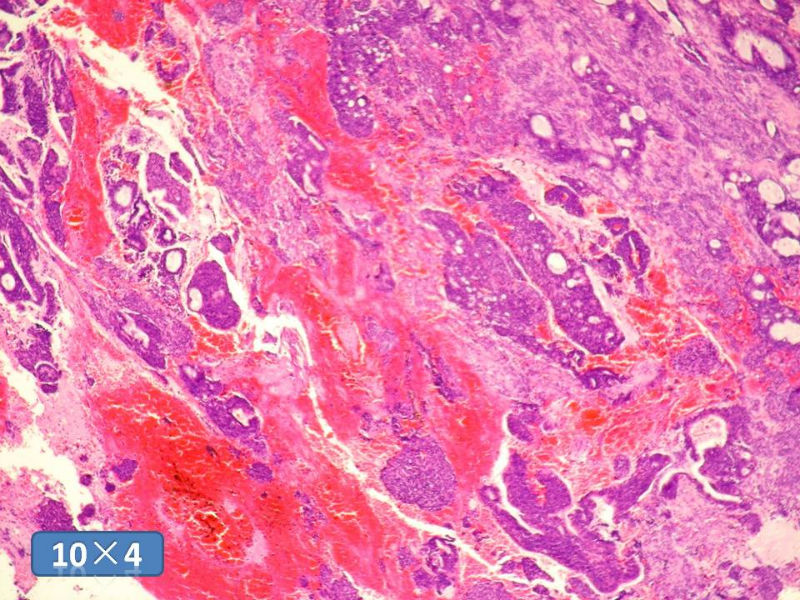

男性,49岁,间断左鼻腔出血3个月。

标签:是嗅母么?

1)嗅神经母细胞瘤?

2)腺肌上皮癌?

3)肌上皮癌?

4)神经内分泌癌?

5)腺样囊性癌?

6)其他?

腺肌上皮癌

感觉要排除畸胎癌肉瘤。

间质为恶性梭形细胞成分,其间感觉是腺体,两种成分密切相关....

免疫组化S-100的阳性区域方式...嗅母可能性大。

支持嗅神经母细胞瘤(伴有腺体分化)

嗅神经母细胞瘤

有上皮和间叶2种结构,畸胎性癌肉瘤是要考虑一下的吧!